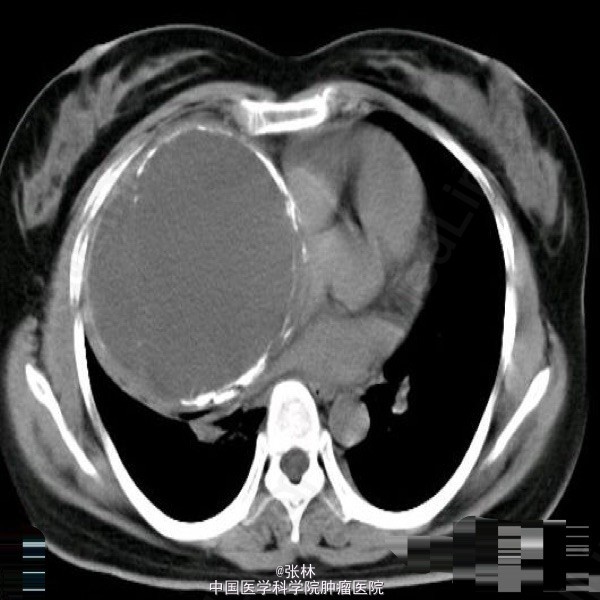

【临床病史】:患者,女性,37岁,运动后心慌、胸闷三年。右胸部呼吸音消失。叩诊呈实音。X线:右侧胸腔占位。 【影像表现】:右侧胸腔巨大囊性低密度影,大小约为109mmx118mm,边界清晰,边缘可见蛋壳样钙化,密度不均匀,CT值-35-420HU。 【影像诊断】:纵隔畸胎瘤 【最后诊断】:病理诊断:前纵隔囊性成熟性畸胎瘤。 【讨论】:畸胎类肿瘤分为囊性和实性两类,囊性畸胎瘤即皮样囊肿,多发生在前纵隔,CT为诊断该肿瘤最佳的影像学方法,可很好地显示肿块内的钙化、骨骼及脂肪成分。